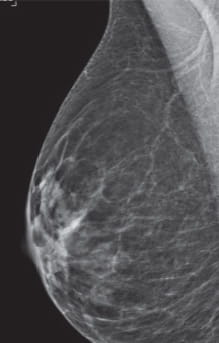

Radiologists classify breast density using a four-level density scale, as determined by a mammogram:

- Category A: Almost entirely fatty

- Category B: Scattered areas of dense breast tissue

- Category C: Heterogeneously dense

- Category D: Extremely dense

Having dense breast tissue may increase your chance of getting breast cancer. Dense breasts also make it more difficult for doctors to spot cancer on mammograms. Dense tissue appears white on a mammogram; lumps, both benign and cancerous, also appear white. So mammograms can be less accurate in women with dense breast tissue.